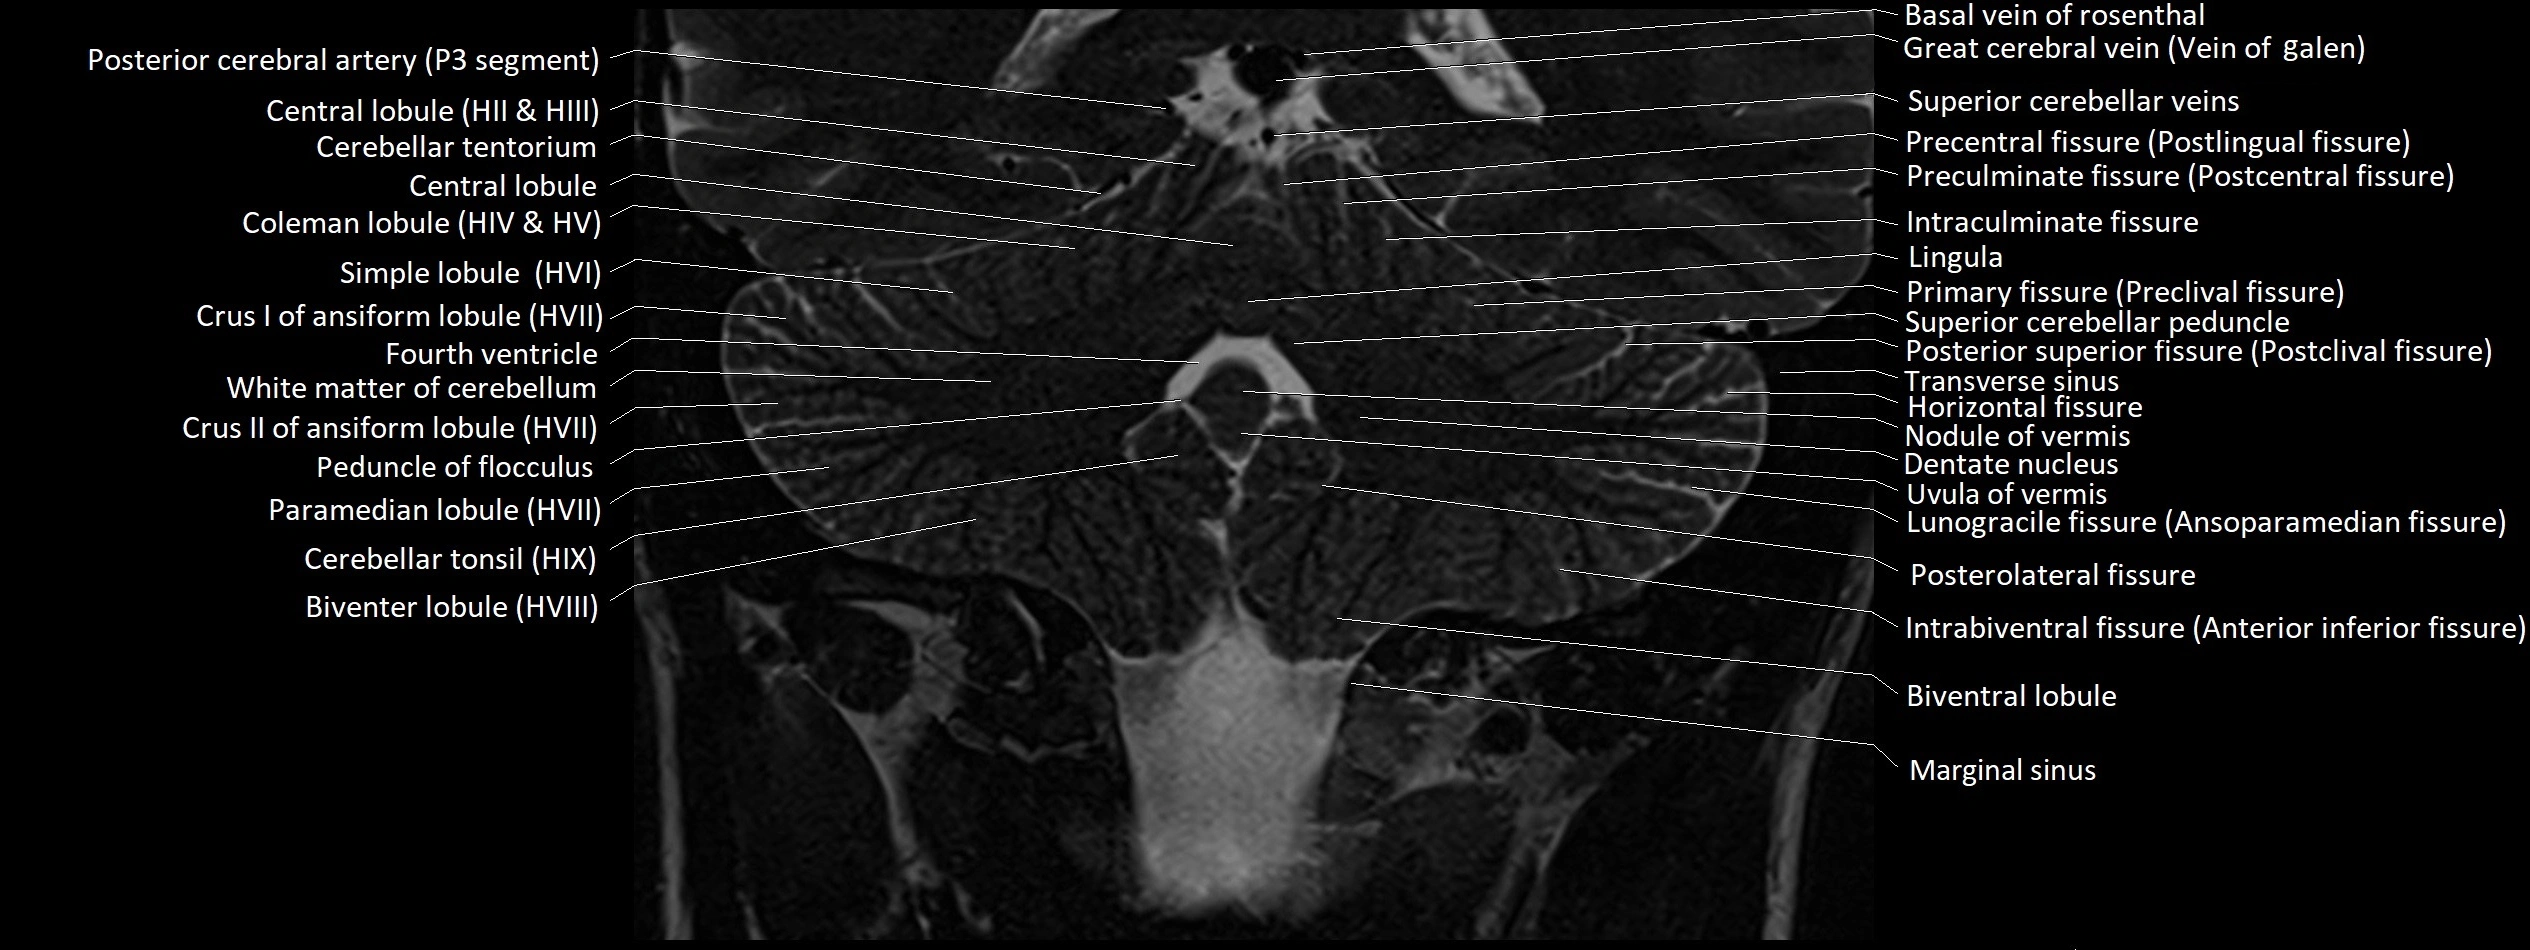

MRI images